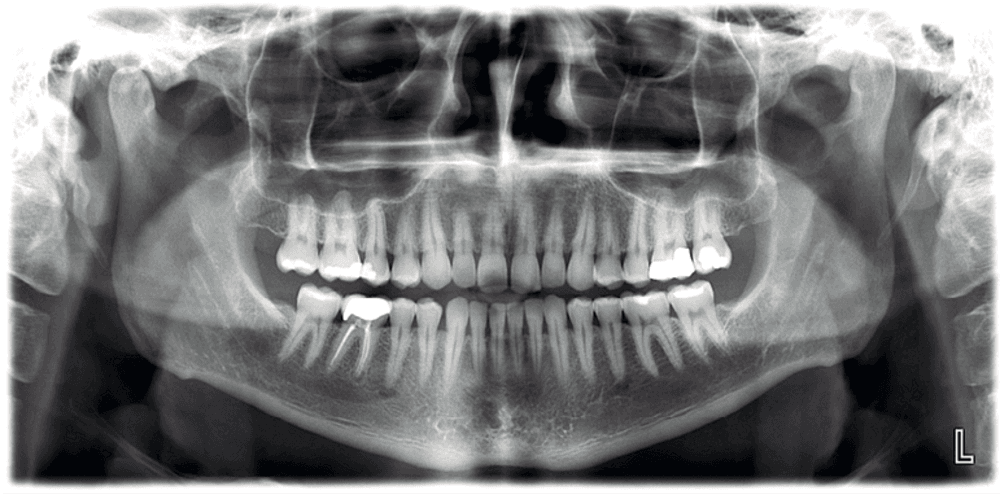

Meet the Planmeca ProMax® 3D imaging family, a comprehensive suite of solutions tailored to meet the unique demands of dental practices. With unparalleled image quality and cutting-edge technology, these systems provide practitioners with the versatility and precision needed for accurate diagnostics and treatment planning.

Discover the Planmeca ProMax® 3D family, meticulously designed to meet the needs of every dental practice. Known for its unparalleled image quality, each system reflects Planmeca's commitment to excellence. Equipped with noise reduction technology, these units deliver unmatched image clarity. Enjoy True Extraoral bitewings, segmented pans, and AutoFocus for crystal clear pan images every time. Available features like Planmeca Ultra Low Dose™ and Planmeca CALM® for patient safety